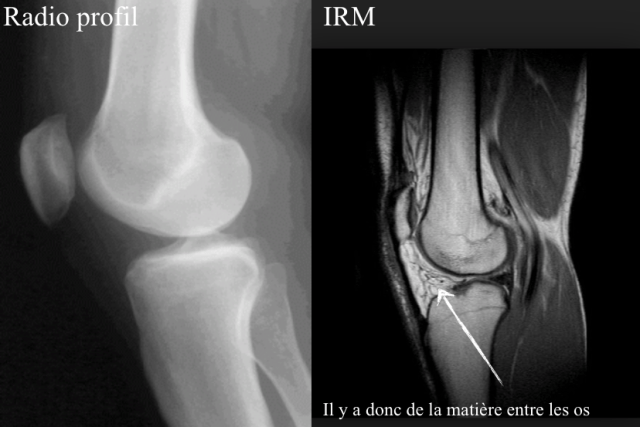

Une articulation normale se reconnaît à la radio par des surfaces osseuses bien lisses, bien dessinées et bien séparées par un espace dont on ne dit souvent rien. En réalité, cet espace est rempli de cartilage et de liquide qui sont traversés par les rayons X, qui ne laissent aucune image (noir sur l’image) donnant ainsi l’impression qu’il n’y a rien entre les os.

Je me suis blessée au genou en m’accroupissant,douleur vive epanchement et emathome prenant tout le tour du genou, très enflé, …

J’ai donc passé une radio sur laquelle était écrit pas de remaniement de gonarthrose. .. seulement 3 semaines après j’ai passé un irm, montrant entre autres soucis une chondropathie avec atteinte sous chondrale de grade 3 voire 4… est il possible de ne rien voir à la radio mais d’avoir un tel diagnostic à l’irm? Je suis perplexe…..